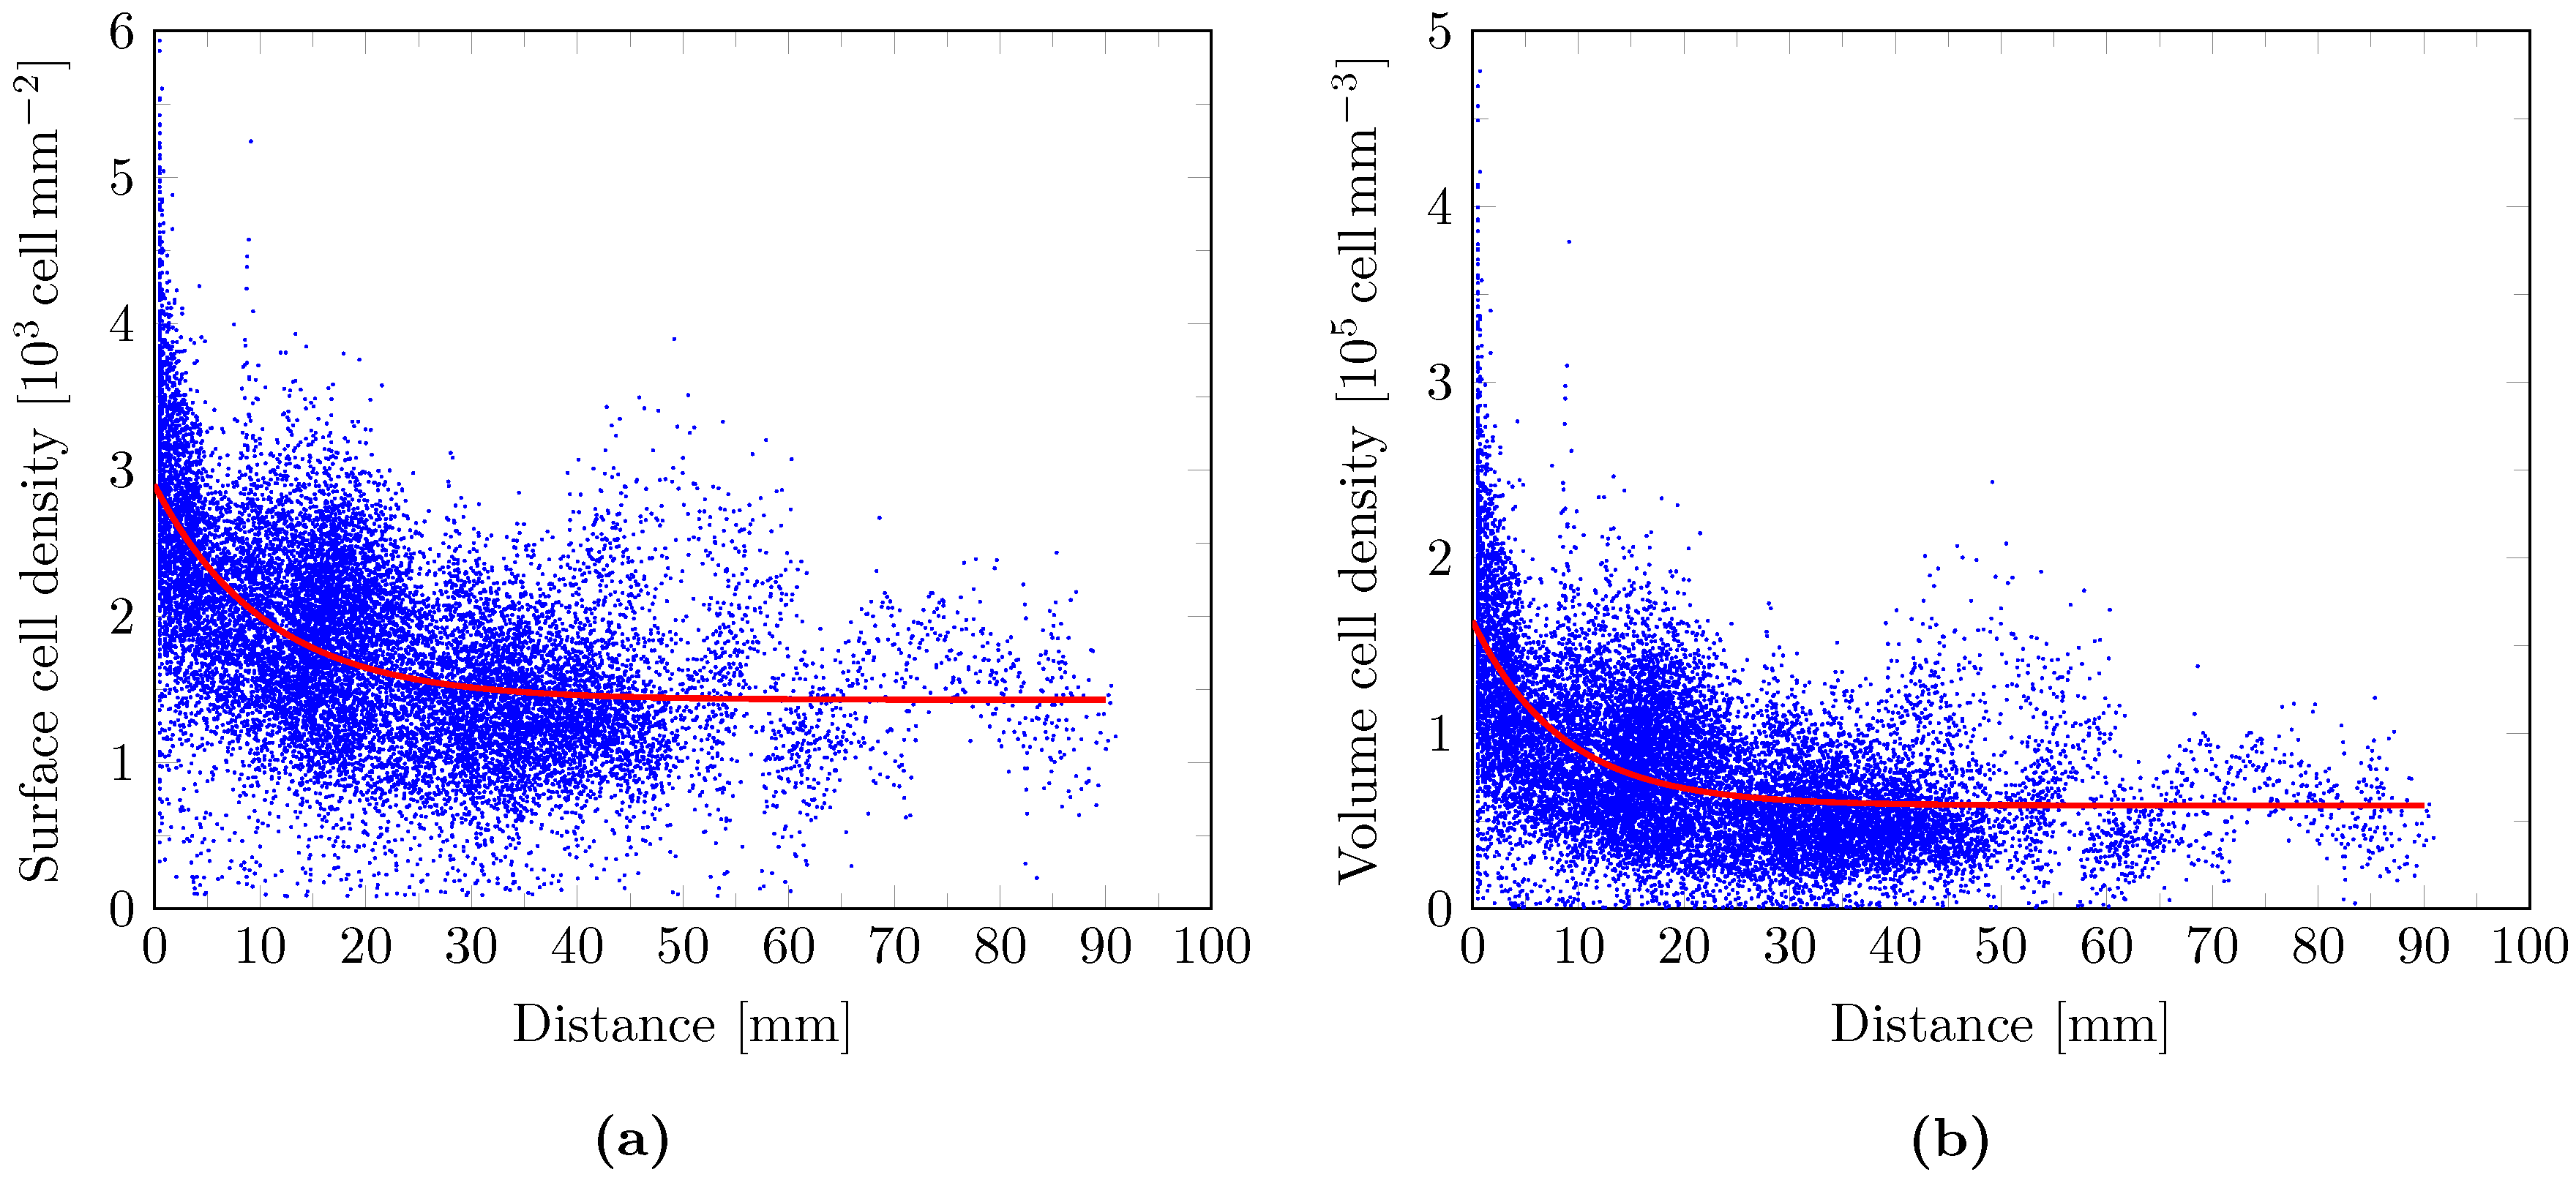

2.9. Cell Density Model

3. Results